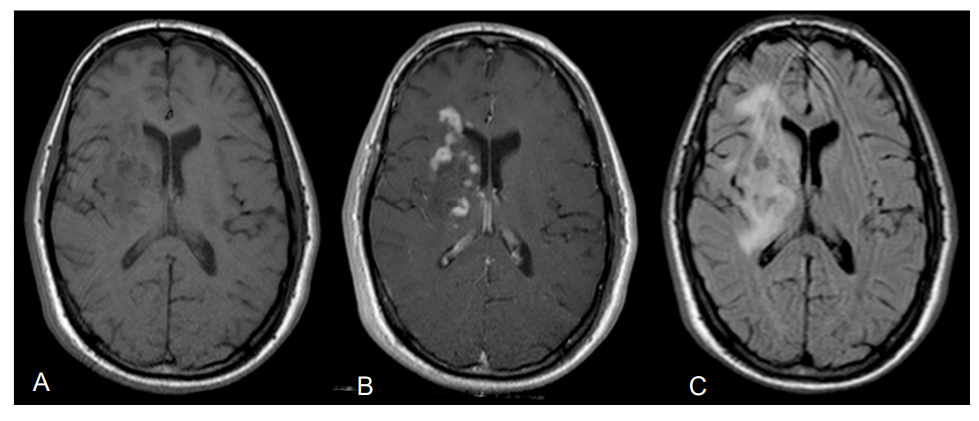

21岁男性,无个人或家族病史,因孤立性进行性左偏瘫而就诊。他没有慢性药物治疗,也没有过敏。临床检查发现孤立性左侧偏瘫。根据医学研究委员会(Medical Research Council)的分级,分段强度评估为4/5。检测相关锥体综合征。未发现颅内压升高综合征的证据。其Karnofsky性能状态指数为90%,体重指数为26 kg/m2。一开始脑部MRI显示右侧额叶、胼胝体和基底节多发增强病灶,并伴有瘤周水肿。全身CT扫描、HIV血清学检查、眼底检查和PET扫描均为阴性,未见异常。患者接受了立体定向肿瘤活检。

图A:轴向t1加权磁共振成像(MRI)。图B:轴位t1加权图像,钆增强,右侧基底节病变增强。图C:轴向液体衰减反转恢复(FLAIR)图像显示右侧基底神经节高信号和瘤周水肿